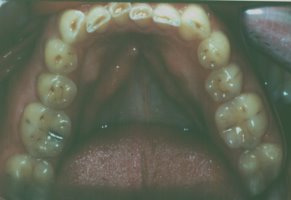

This patient had severely worn

teeth probably due to grinding his teeth in his sleep. There was not

enough room to place crowns on the most severely worn teeth unless root

canal treatment was performed. In this case, we opened his bite with an

orthodontic retainer, and erupted his back teeth with orthodontic rubber

bands. This allowed the back teeth to come together in a proper bite

while at the same time, creating space to place crowns on the three most

severely worn teeth of the group of lower front teeth. Now these teeth

will be protected from further wear for many years to come. |